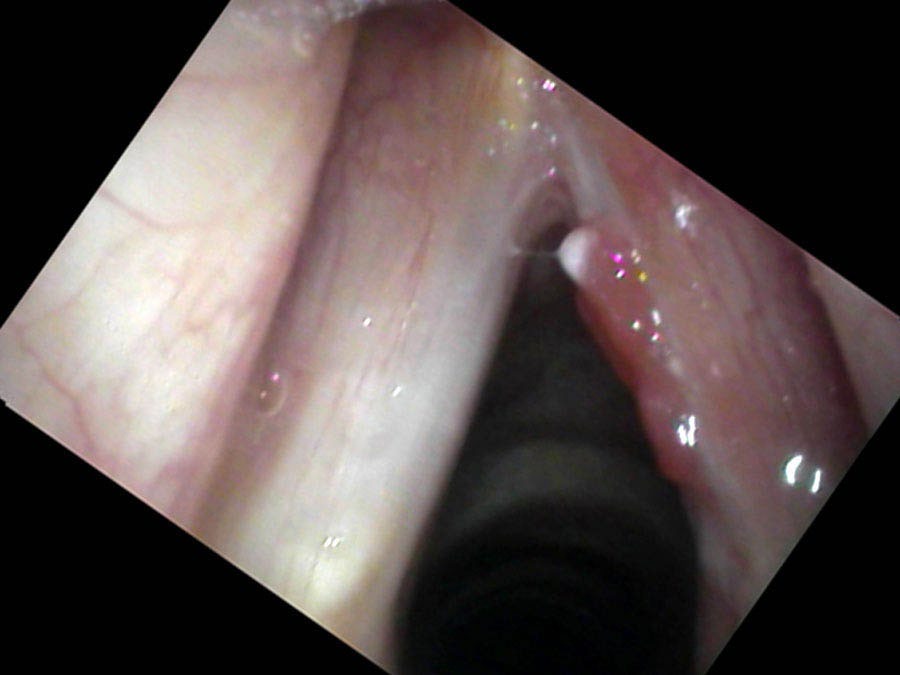

Despite its rather extensive appearance, this cancer proved to be entirely on the surface and was peeled off of the right vocal cord with a CO₂ laser. One month after the surgery he still had a slightly elevated red area on the edge of the vocal cord. While this appeared to be a granuloma on my endoscopic examination, Mr. Kowal now had an elevated concern for any finding that might represent cancer. Since lesions with blood in them respond well to the office pulsed KTP laser, we treated this and the red lumps were gone by his next office visit.

For me, the reason that follow-up examinations are as important as the diagnosis is that I have cut closer to the cancer than many other surgeons. This leaves more normal vocal cord in place.

He returns to the clinic for frequent check-ups and the tumor has not recurred as of writing. Follow-up examinations are important in any patient with cancer. Because of the fear that the word cancer strikes in patients and physicians, there is a tendency to overtreat. Removing Mr. Kowal’s entire larynx with a total laryngectomy would have been equally effective treatment — more certainly it would have removed all of the cancer. However he would now be functioning without a voice box. When I removed Mr. Kowal’s tumor, I cut right on the interface of the tumor and his normal tissue. With regular, close examinations and with high-quality endoscopes, I believe that I will see any remnants or recurrences of the cancer early and can treat them appropriately while still very small.